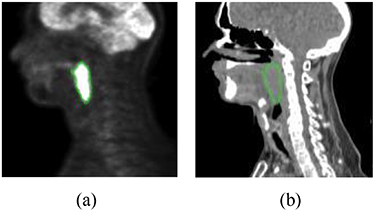

In this study, FDG-PET and radiotherapy planning CT (figure 6) from 188 patients are used. All these patients had pre-treatment FDG-PET/CT scans between April 2006 and November 2017, which were downloaded from the cancer imaging archive (TCIA) (Vallières et al 2017). The follow up time ranges from 6 months to 112 months and the median follow up are about 43 months. Sixteen percent (16%) of these patients had distant metastasis. We also used clinical parameters extracted from clinical charts, including gender, age, T stage, N stage, M stage, TNM group stage. There are 257 features extracted from PET and CT images, respectively, including intensity, texture and geometry features.

Figure 6. Illustration of FDG-PET and CT images. The green contour is the tumor: (a) FDG-PET and (b) CT.